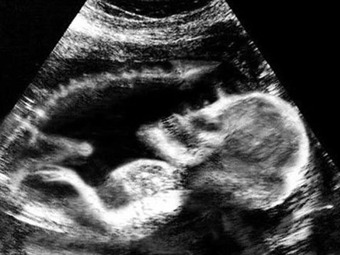

Cada vez que llega un nuevo ser la familia se llena de alegría, inclusive buscan la forma de imaginarlo y verlo lo antes posible por lo que se hacen ecografías.

Desafortunadamente algunos padres no han tenido una buena experiencia, por el contrario han salido llenos de horros.

Extrañas, espantosas y espectrales figuras que salen en el ultrasonido.

figuras espantosas y espectrales.